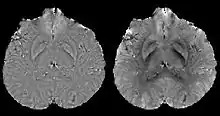

Background field removal

In human brain quantitative susceptibility mapping, only the local susceptibility sources inside the brain are of interest. However, the magnetic field induced by the local sources is inevitably contaminated by the field induced by other sources such as main field inhomogeneity (imperfect shimming) and the air-tissue interface, whose susceptibility difference is orders of magnitudes stronger than that of the local sources. Therefore, the non-biological background field needs to be removed for clear visualization on phase images and precise quantification on QSM.

Ideally, the background field can be directly measured with a separate reference scan, where the sample of interest is replaced by a uniform phantom with the same shape while keeping the scanner shimming identical. However, for clinical application, such an approach is impossible and post-processing based methods are preferred. Traditional heuristic methods, including high-pass filtering, are useful for the background field removal, although they also tamper with the local field and degrade the quantitative accuracy.

More recent background field removal methods directly or indirectly exploit the fact that the background field is a harmonic function. Two recent methods based on physical principles, projection onto dipole fields (PDF)[8] and sophisticated harmonic artifact reduction on phase data (SHARP),[9] demonstrated improved contrast and higher precision on the estimated local field. Both methods model the background field as a magnetic field generated by an unknown background susceptibility distribution, and differentiate it from the local field using either the approximate orthogonality or the harmonic property. The background field can also be directly computed by solving the Laplace's equation with simplified boundary values, as demonstrated in the Laplacian boundary value (LBV) method.[10]

Differentiating calcification from iron

It has been confirmed in in vivo and phantom experiments that cortical bones, whose major composition is calcification, are diamagnetic compared to water.[11][18] Therefore, it is possible to use this diamagnetism to differentiate calcifications from iron deposits that usually demonstrate strong paramagnetism.[19] This may allow QSM to serve as a problem solving tool for the diagnosis of confounding hypointense findings on T2* weighted images.